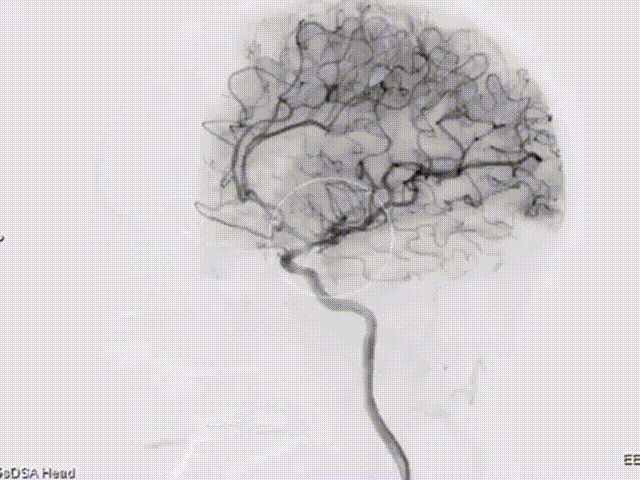

术后造影及三维重建。